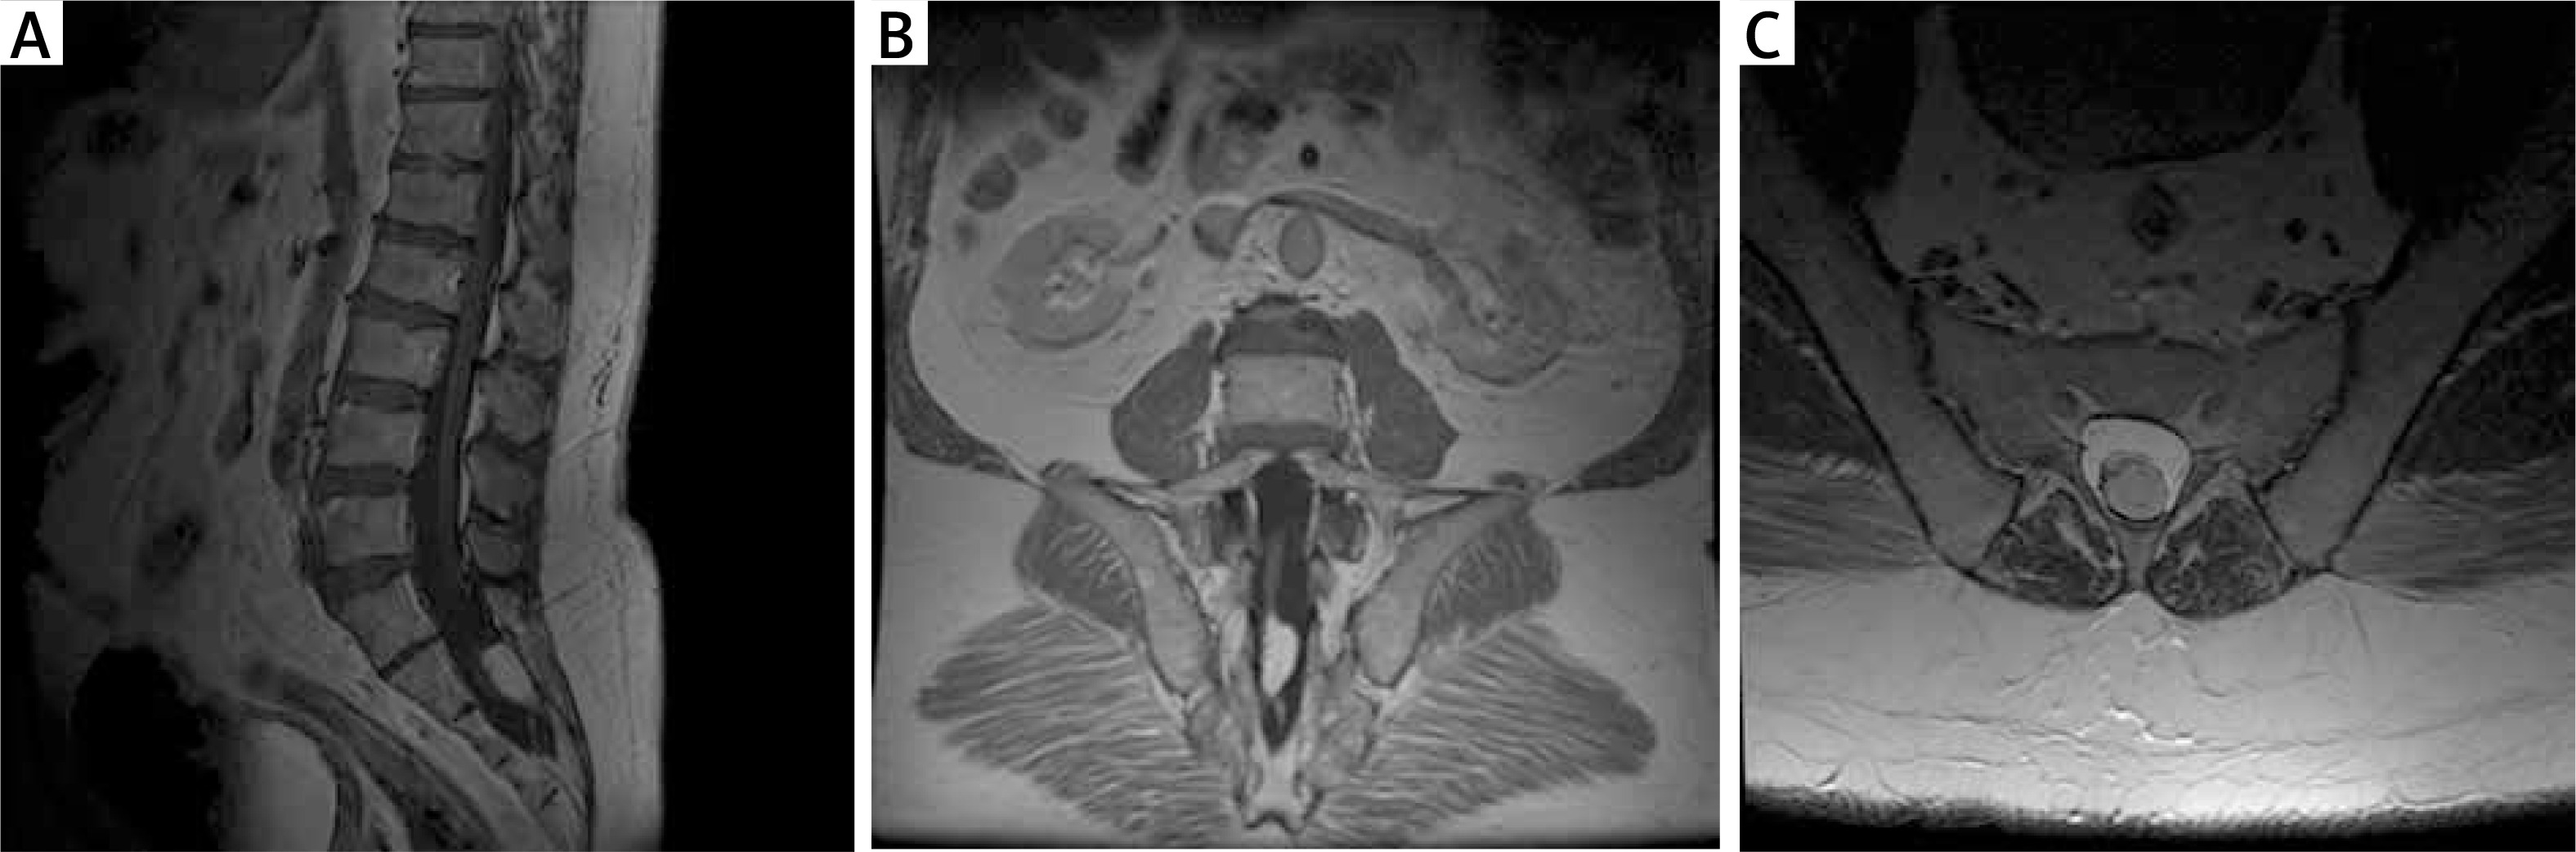

Magnetic resonance imaging (MRI) of the lumbosacral (L/S) spine

An MRI scan (1.5 T) showed a low-terminal spinal cone at the S2 level with a thickened terminal nerve, as well as a lesion with a high signal at T2 time, which corresponds to an intramedullary adipoma spreading into the subcutaneous tissue through the unattached L5 arch. The image corresponding to the first type of TCS can be observed in Figure 1.

Figure 1

Pre-operative MRI examination of the first patient. A – T1 FSE S time with contrast; visible end-striatal fatoma and non-union of L5 and S1 arch. B – T2 time. C – axial sections at T2 time; widening of the spinal canal, filled with adipoma. D – axial sections at T1 time with contrast; the tumour shows no contrast enhancement